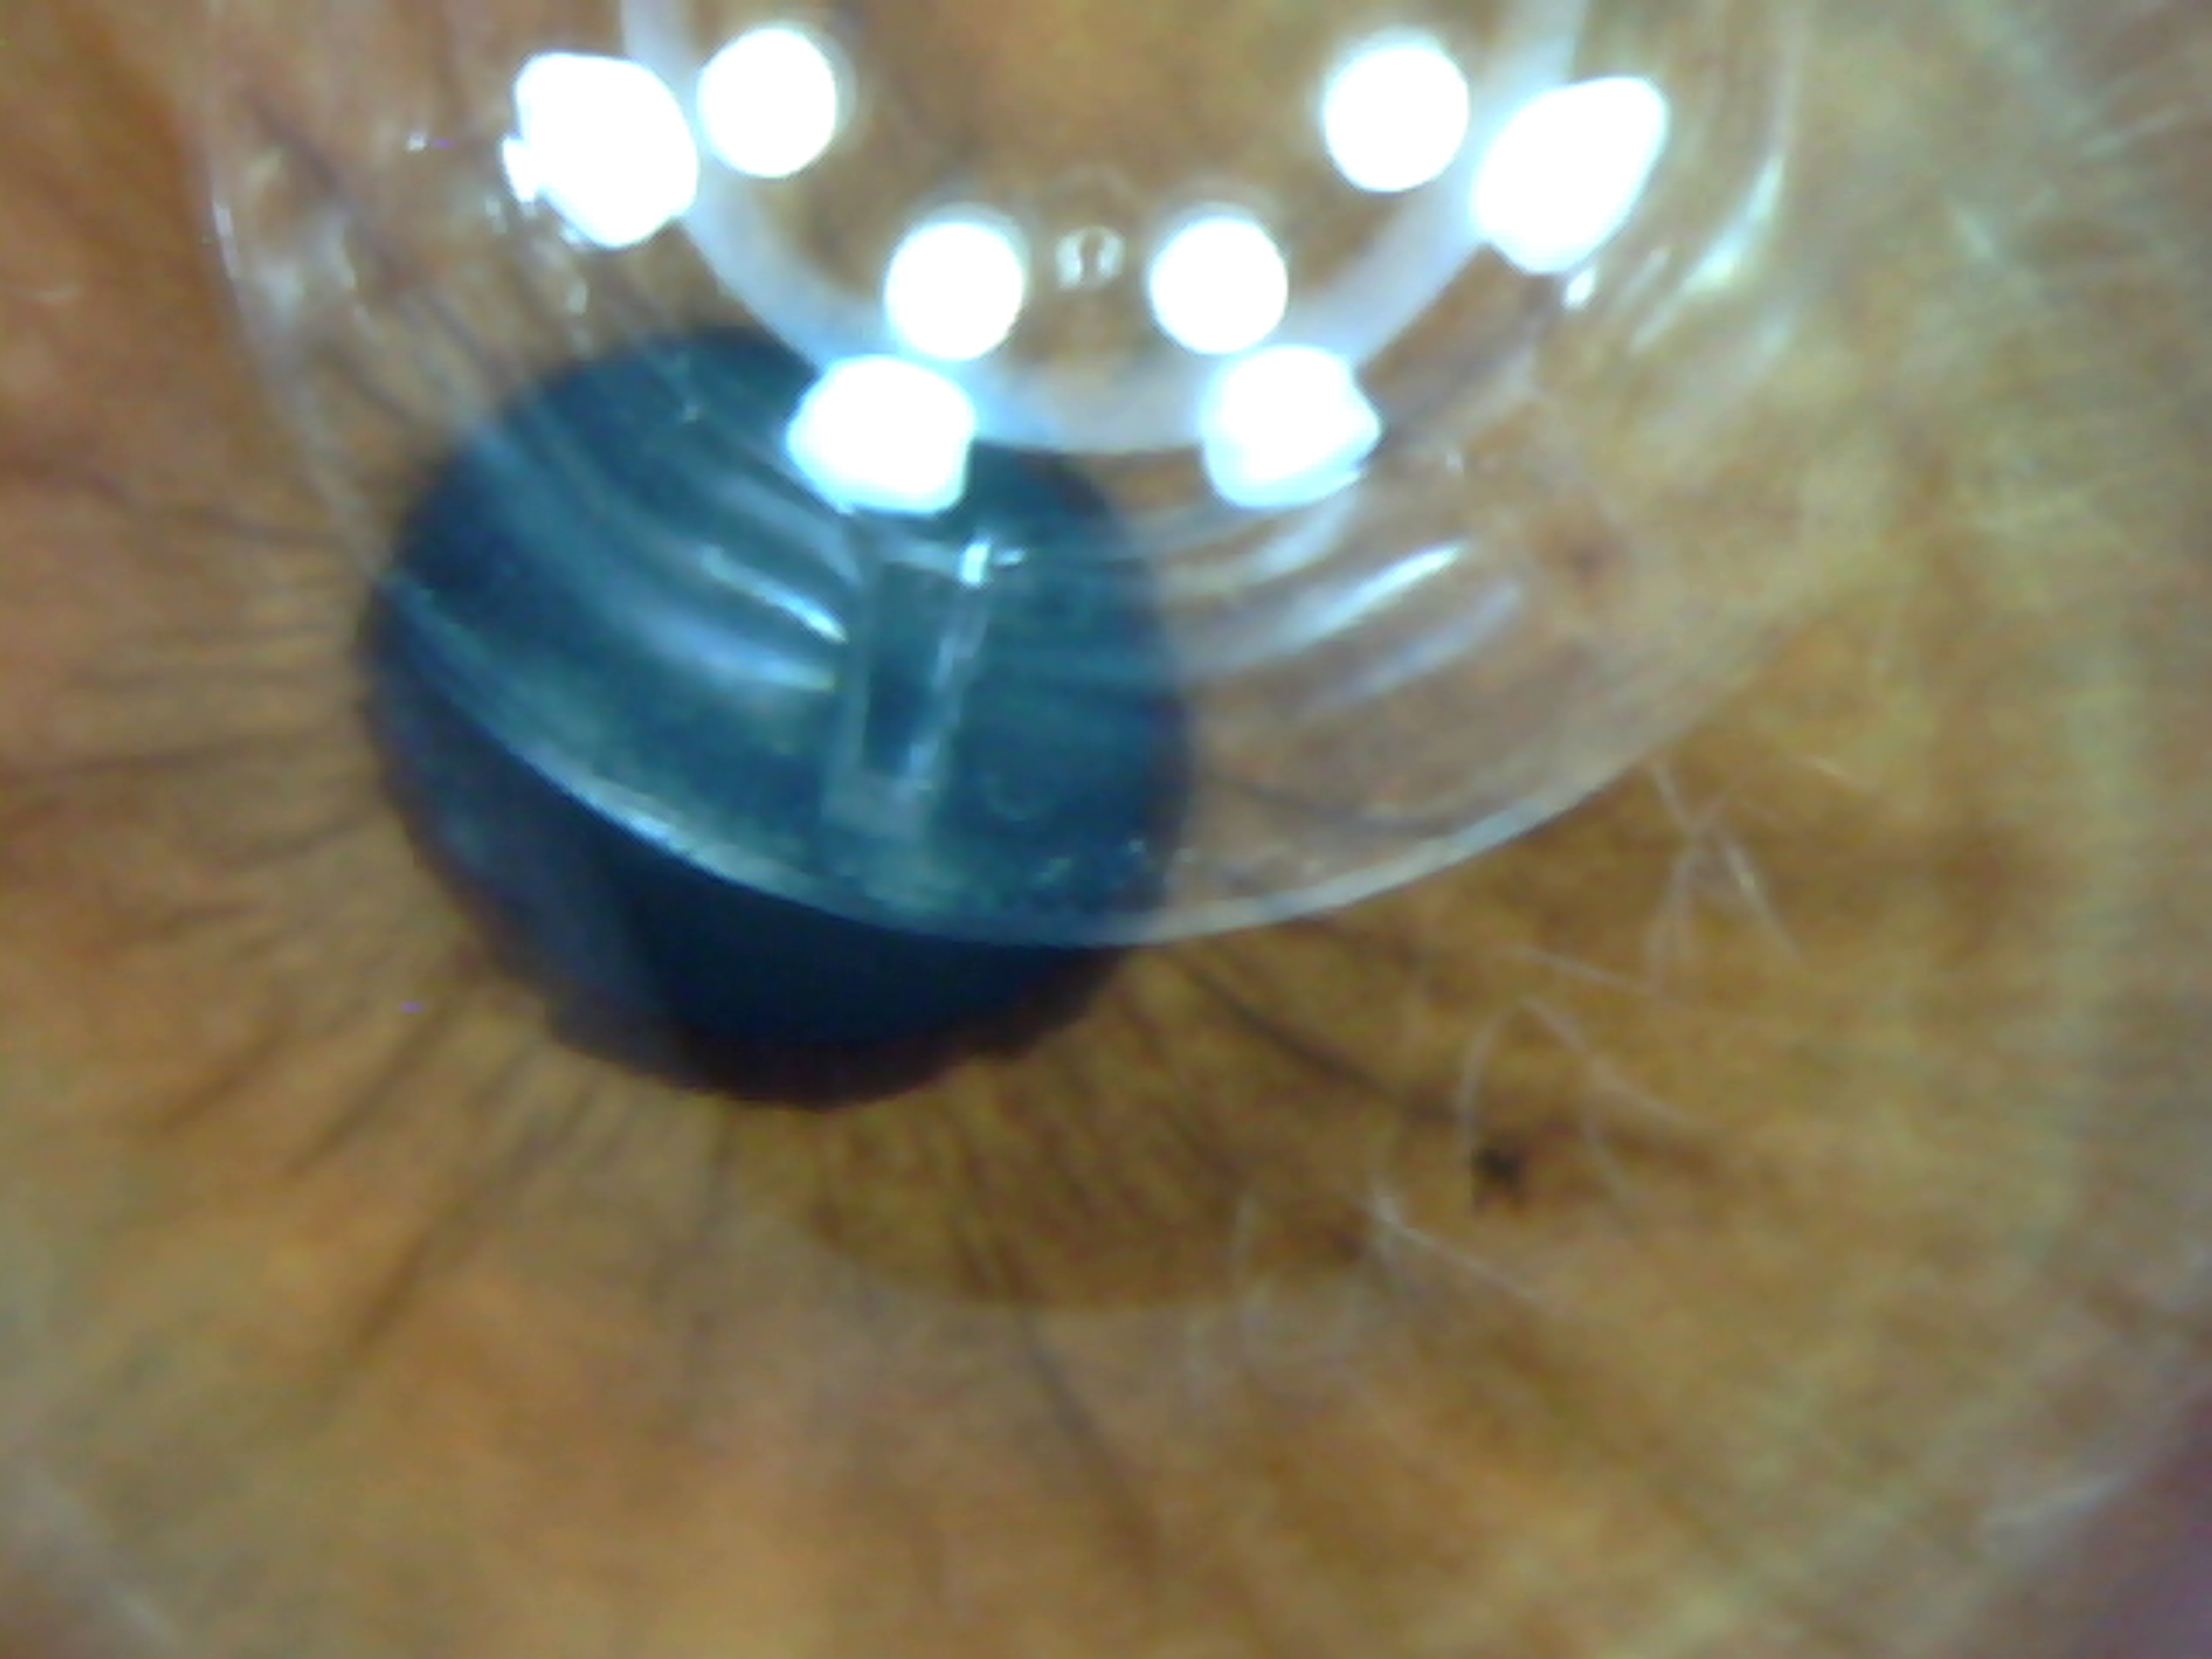

Derma